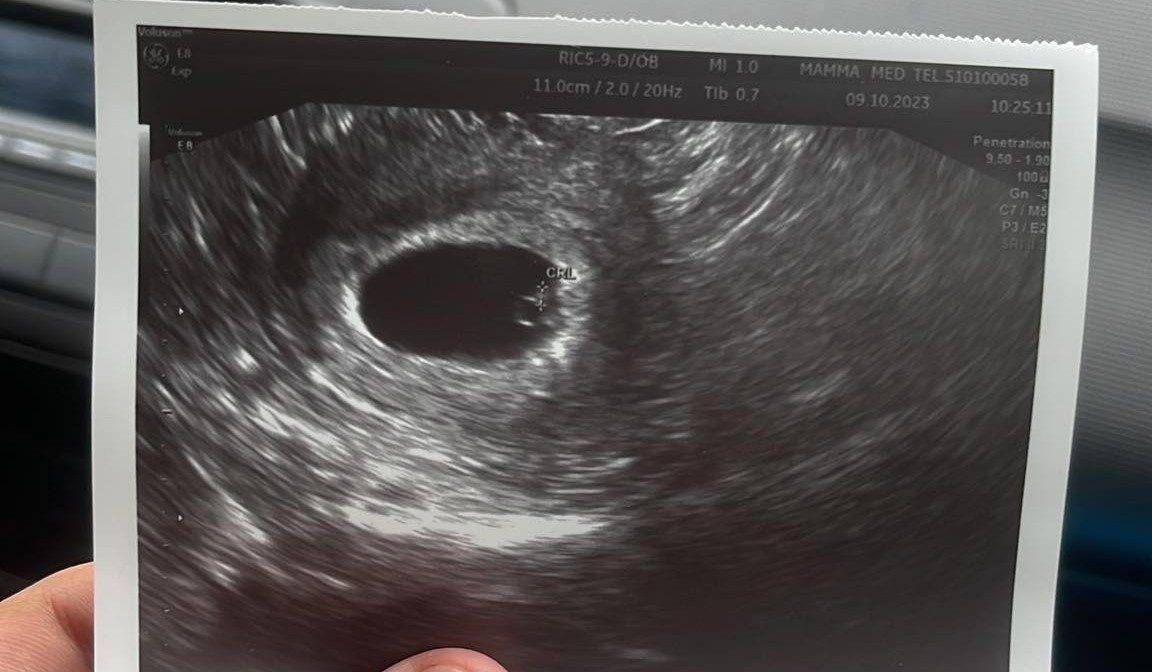

Mam pamiątkowe pudło z pierwszej ciąży i z pierwszych rzeczy córeczki. Typu , smoczki, pierwsza butelka, karuzela, pierwszy gryzak,miś, buciki w których zaczęła chodzić, pamiątki z chrztu, karta ciąży , ubranko w którym wyszła ze szpitala, pępowinę i takie tam różne. I tak właśnie przeglądam zdjęcia z USG. I mam zdjęcie z 8 tygodnia. Już widać ładnie główkę itp.

W czwartek będę miała 6+3 ale na prywatnej wizycie po 20ym października będę 8+3 to pewnie będzie widać podobnie <3